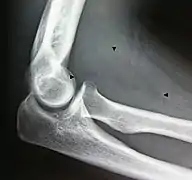

- استئصال ورم شحمي عضلي في منطقة الكوع

صورة أثناء العملية.

مجال التشغيل بعد إزالة الورم الشحمي: يمثل السهم العصب الوسيط الذي تم ضغطه بواسطة الورم الشحمي.

ورم شحمي مقطوع

(8 cm × 6 cm × 3 cm)